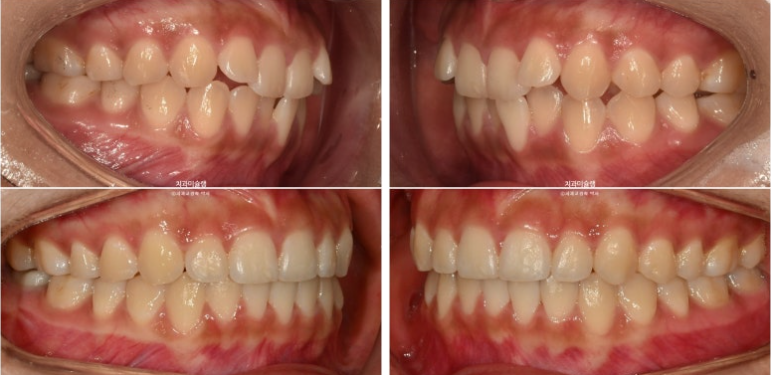

24년 여름방학을 이용해서 교정상담을 온 유학생 환자분입니다.

측절치의 개방교합, 아래 앞니 덧니 등 보입니다.

우측 교합관계는 1급에 가깝지만

좌측 교합관계는 2급입니다.

사랑니를 빼고 사랑니 공간으로 어금니를 후방이동 시켜 교합관계를 맞추고 덧니 해소할 공간을 얻기로 합니다.

어금니 후방이동을 위해 교정용 나사 미니스크류가 안팎으로 심겨져있습니다.

치료시작 11개월 차, 첫 세트의 48개 장치를 모두 낀 후 모습입니다.

중심선이 아직 약간 어긋나 있지만 덧니와 개방교합은 개선되었습니다.

좌측의 2급 교합이 아직 남아있습니다.

중심선은 맞아졌고

어금니 교합은 좌우 모두 1급 교합관계를 달성